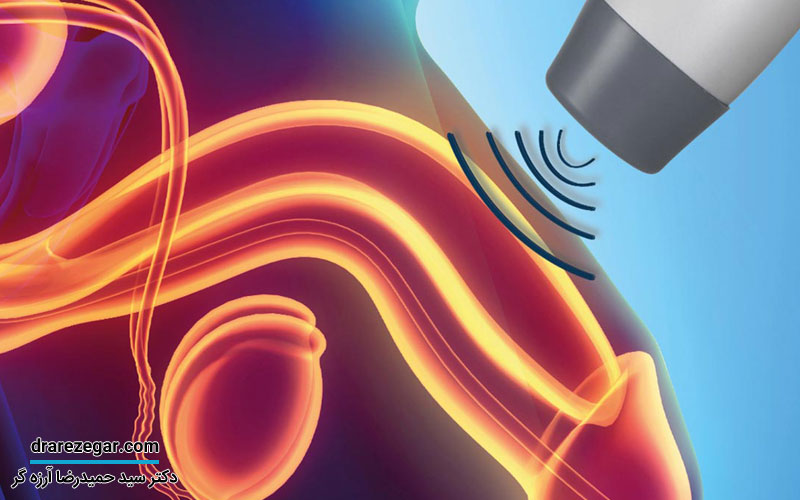

تشخیص افتادگی مثانه

با بررسی سابقه پزشکی و معاینه لگن می توان افتادگی مثانه را تشخیص داد. برای تشخیص دقیق تر و این که چه قسمت هایی از واژن دچار افتادگی شده است، تست های تشخیصی دیگری انجام می شوند که برخی از آن ها شامل موارد زیر هستند:

• تصویربرداری با اشعه ایکس

• ام آر آی

• سونوگرافی

• سیستوسکوپی

• نوار مثانه